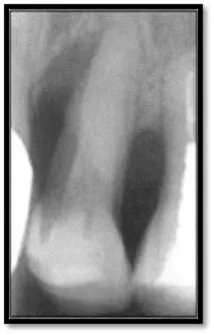

Initial perio charting (above left), Pretreatment radiograph (above right)

As you can see, calculus is visible on the mesial surfaces of both molars and the extent of bone loss mesial of # 30 is significant. 18 months post treatment: